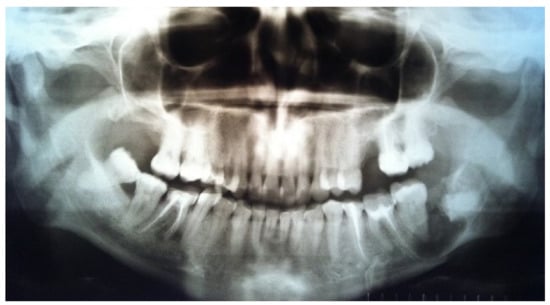

The orthopantomogram showed a fracture line in the area of tooth 3.8 and an oval-shaped area of radiolucency with teeth 3.7 and 3.8, with root involvement (Figure 1).

Figure 1.

Orthopantomogram before surgery.